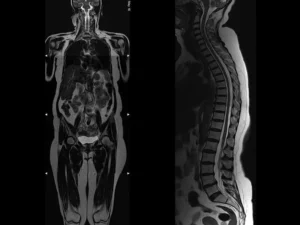

Tüm vücut MR, manyetik rezonans görüntüleme teknolojisi kullanılarak vücudun tamamının ayrıntılı bir şekilde taranmasıdır. Radyasyon içermeyen bu yöntem, manyetik alan ve radyo dalgaları yardımıyla organların ve dokuların yapısını detaylı bir şekilde gösterir. Doktorlar, bu görüntüleri kullanarak hastalıkları teşhis eder ve tedavi planlarını oluşturur.

Tüm vücut MR, genellikle hastalıkların erken teşhisi ve yayılımının değerlendirilmesi amacıyla çekilir. Özellikle kanser taramaları, inflamatuar hastalıklar, enfeksiyonlar ve dejeneratif hastalıkların tespitinde kullanılır. Ayrıca, vücutta mevcut olan anormalliklerin detaylı bir şekilde incelenmesi için de tercih edilir.

Tüm vücut MR, kanser şüphesi olan hastalarda, inflamatuar hastalıklarda, enfeksiyonların yayılımını belirlemek için ve dejeneratif hastalıkların teşhisinde kullanılır. Ayrıca, kronik ağrıların kaynağını tespit etmek, sinir sistemi hastalıklarını ve damar problemlerini değerlendirmek amacıyla da uygulanabilir.

Tüm vücut MR ile kanser türleri, tümörlerin yayılımı, inflamatuar hastalıklar, enfeksiyonlar, dejeneratif hastalıklar, sinir sistemi bozuklukları ve damar hastalıkları teşhis edilebilir. Bu yöntem, özellikle erken teşhis gerektiren hastalıklarda büyük önem taşır ve doktorların doğru tedavi yöntemini belirlemelerine yardımcı olur.